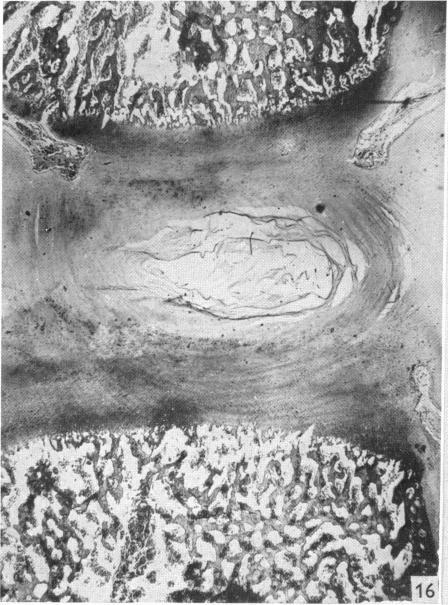

Observations on the prenatal development of the intervertebral disc in man.

J Anat. 1951 Jul;85(3):260-74.